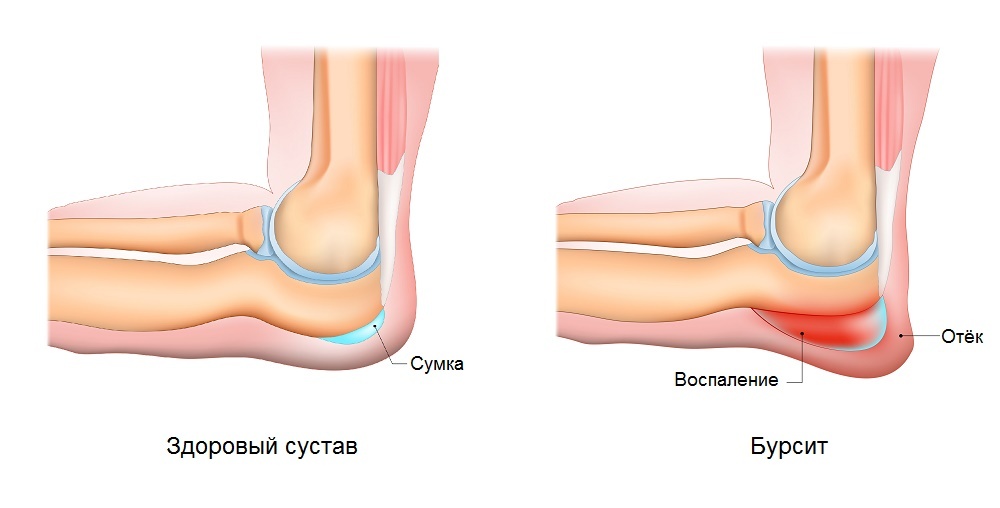

Заболевание сустава: симптомы и лечение